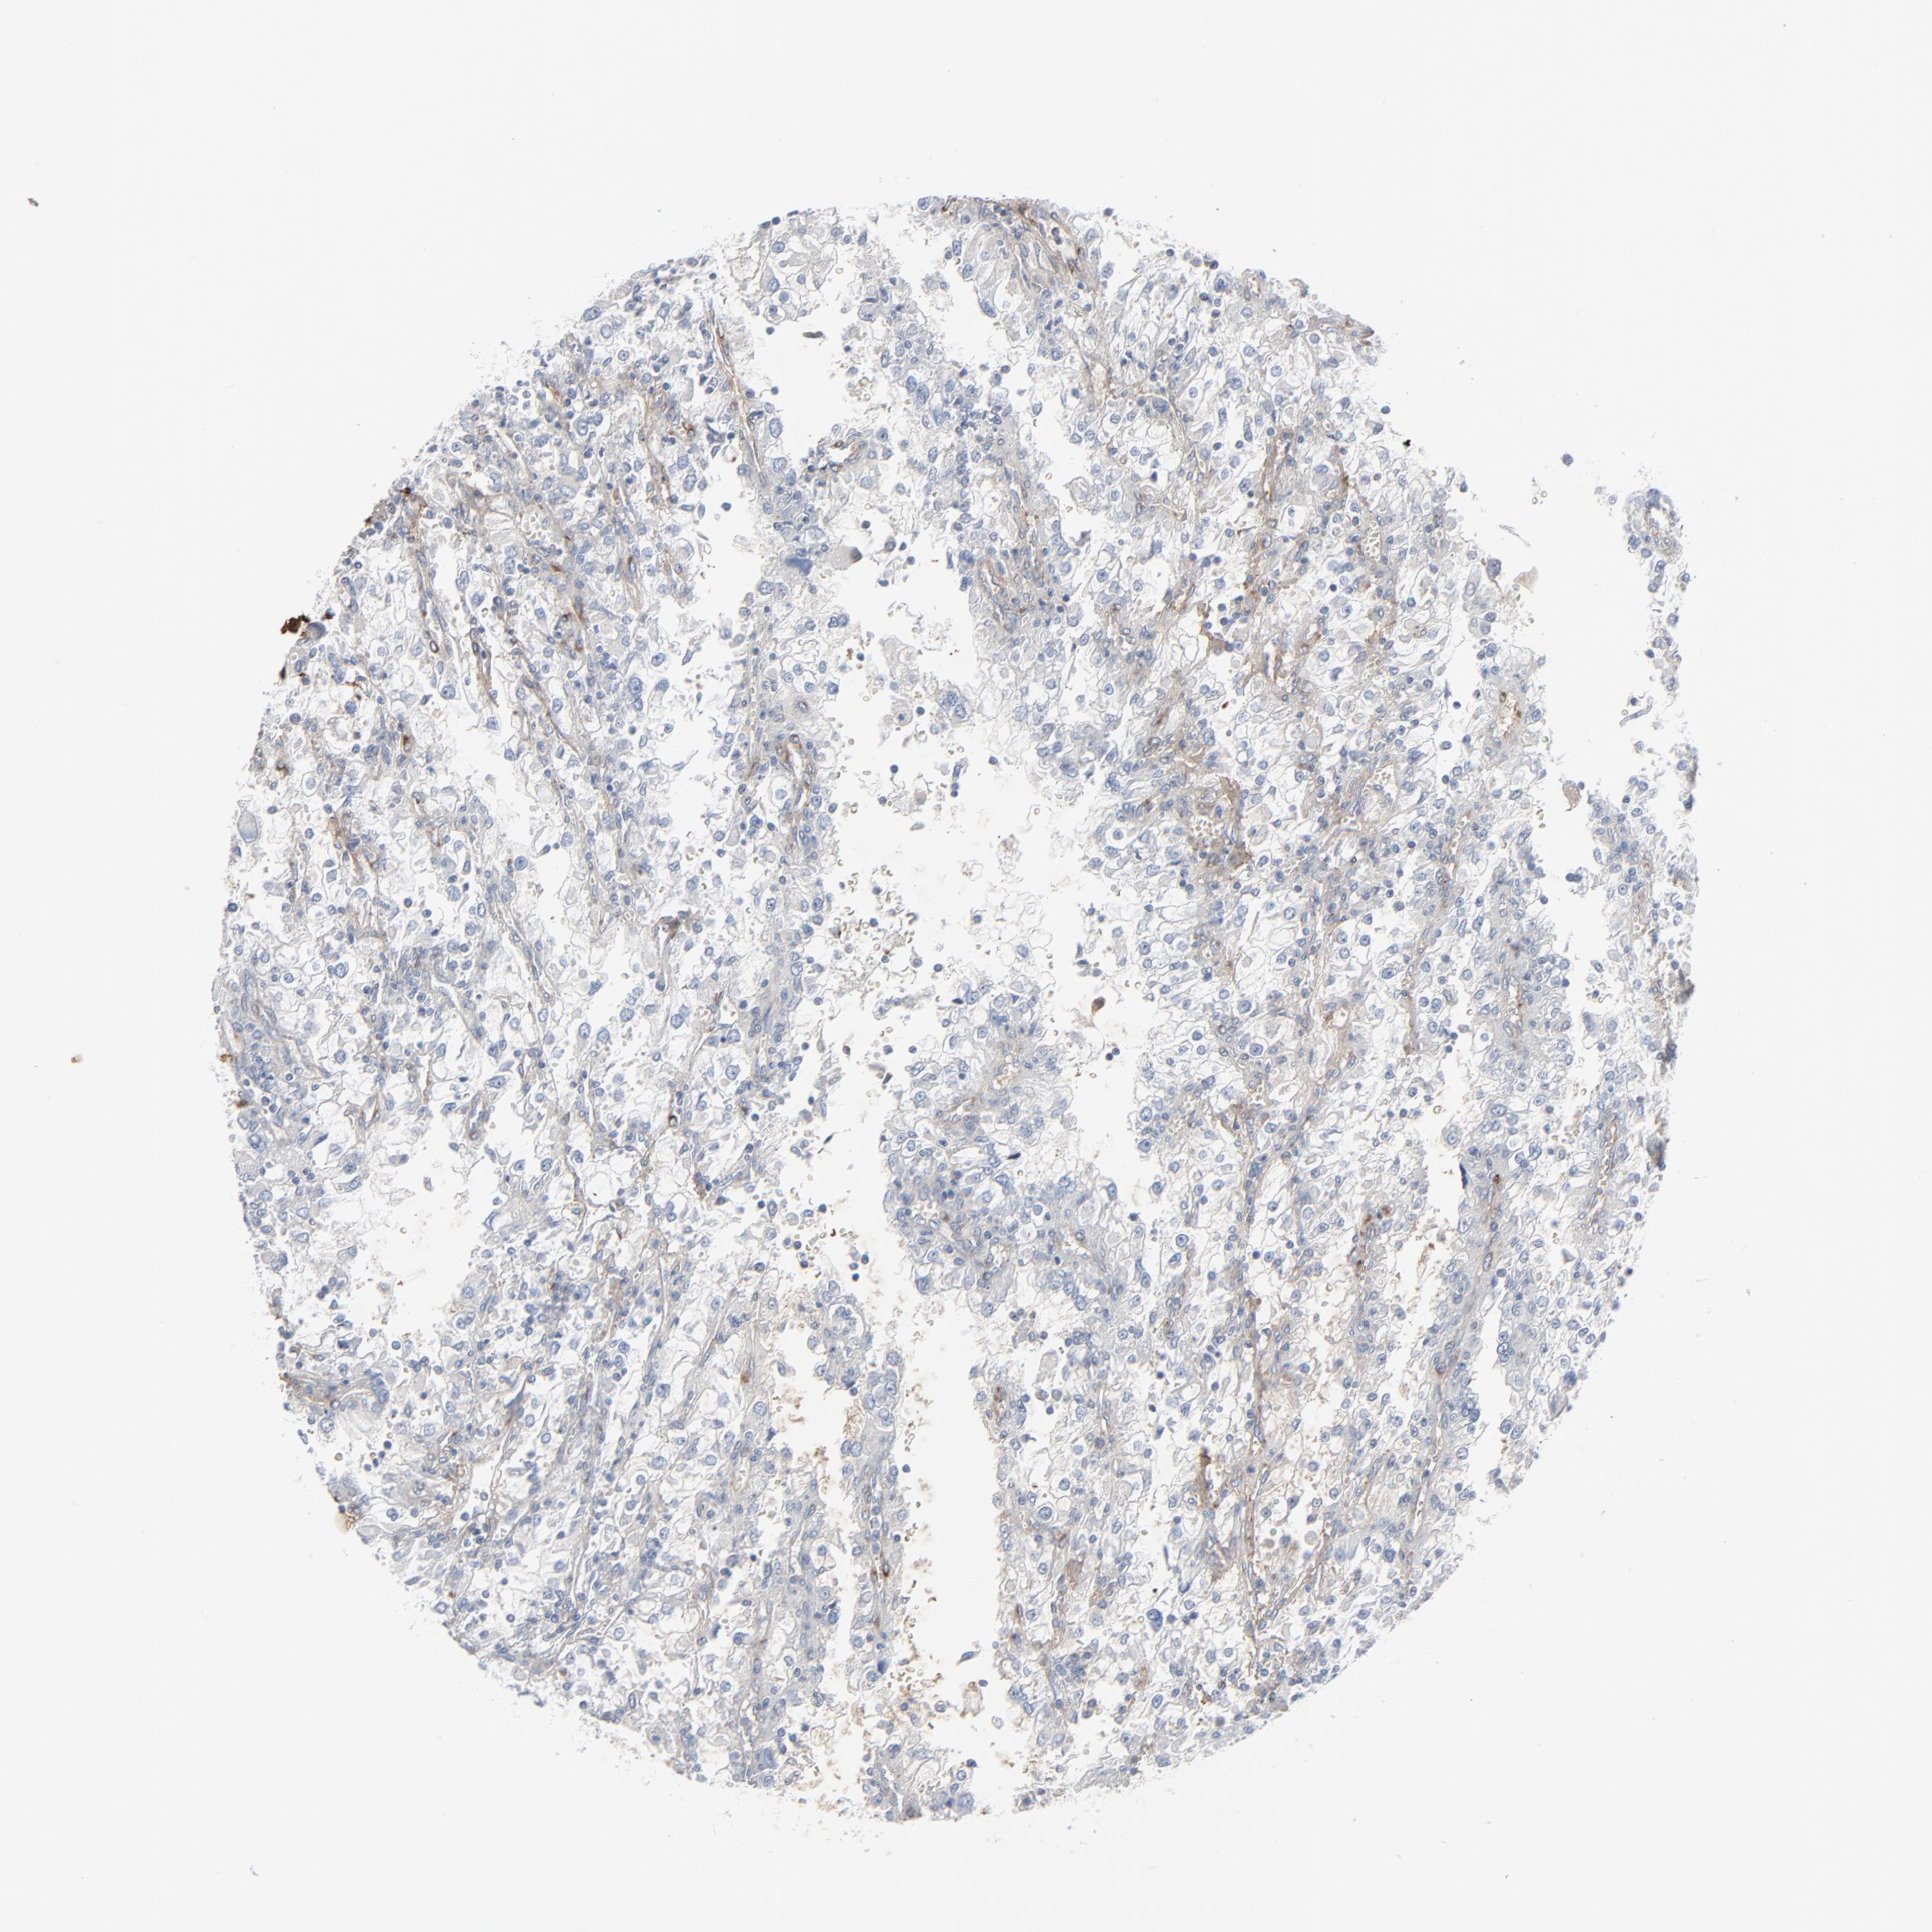

KIDNEY RENAL CLEAR CELL CARCINOMA (VALIDATION) - Interactive survival scatter ploti

The Survival Scatter plot shows the clinical status (i.e. dead or alive) for all individuals in the patient cohort, based on the same data that underlies the corresponding Kaplan-Meier plots. Patients that are alive at last time for follow-up are shown in blue and patients who have died during the study are shown in red.

The x-axis shows the expression levels (FPKM) of the investigated gene in the tumor tissue at the time of diagnosis. The y-axis shows the follow-up time after diagnosis (years). Both axes are complimented with kernel density curves demonstrating the data density over the axes. The top density plot shows the expression levels (FPKM) distribution among dead (red) and alive patients (blue). The right density plot shows the data density of the survived years of dead patients with high and low expression levels respectively, stratified using the cutoff indicated by the vertical dashed line through the Survival Scatter plot. This cutoff is automatically defined based on the FPKM cutoff that minimizes the p-score. The cutoff can be changed by dragging the vertical line or by entering a cutoff value in the square labeled "Current cut-off".

Under the Survival Scatter plot the p-score landscape (black curve; left axis) is shown together with dead median separation (red curve; right axis). Dead median separation is the difference in median mRNA expression between patients who have died with high and low expression, respectively. It is calculated as follows: median FPKM expression of dead patients with high expression - median FPKM expression of dead patients with low expression. This is intended to aid the user in visually exploring custom cutoffs and the associated p-scores and dead median separation.

Individual patient data is displayed and can be filtered by clicking on one or more of the category buttons on the top of the page. Categories describing expression level and patient information include: high, low, alive, dead, female, male and tumor stages. The scale of the x-axis can be toggled between linear and log-scale by clicking on the "x log" button. Mouse-over function shows TCGA ID, patient information and mRNA expression (FPKM) for each patient.

& Survival analysisi

Kaplan-Meier plots summarize results from analysis of correlation between mRNA expression level and patient survival. Patients were divided based on level of expression into one of the two groups "low" (under cut off) or "high" (over cut off). X-axis shows time for survival (years) and y-axis shows the probability of survival, where 1.0 corresponds to 100 percent.

BGN is not prognostic in Kidney Renal Clear Cell Carcinoma (validation)

Best expression cut offi

Based on the FPKM value of each gene, patients were classified into two groups and association between prognosis (survival) and gene expression (FPKM) was examined. The best expression cut-off refers the FPKM value that yields maximal difference with regard to survival between the two groups at the lowest log-rank P-value. Best expression cut-off was selected based on survival analysis .

When clicking on this number, the vertical dashed line indicating cut-off, the interactive survival plot, and the Kaplan-Meier curve will be adjusted to show results based on the best expression cut-off.

: 154.57

TCGA RNA samplesi

RNA-seq data is reported as average FPKM (number Fragments Per Kilobase of exon per Million reads), generated by the The Cancer Genome Atlas (TCGA) .

Normal distribution across the dataset is visualized with box plots, shown as median and 25th and 75th percentiles. Points are displayed as outliers if they are above or below 1.5 times the interquartile range. FPKM values of the individual samples are presented next to the box plot.

Average pTPM 316.7

Number of samples 100